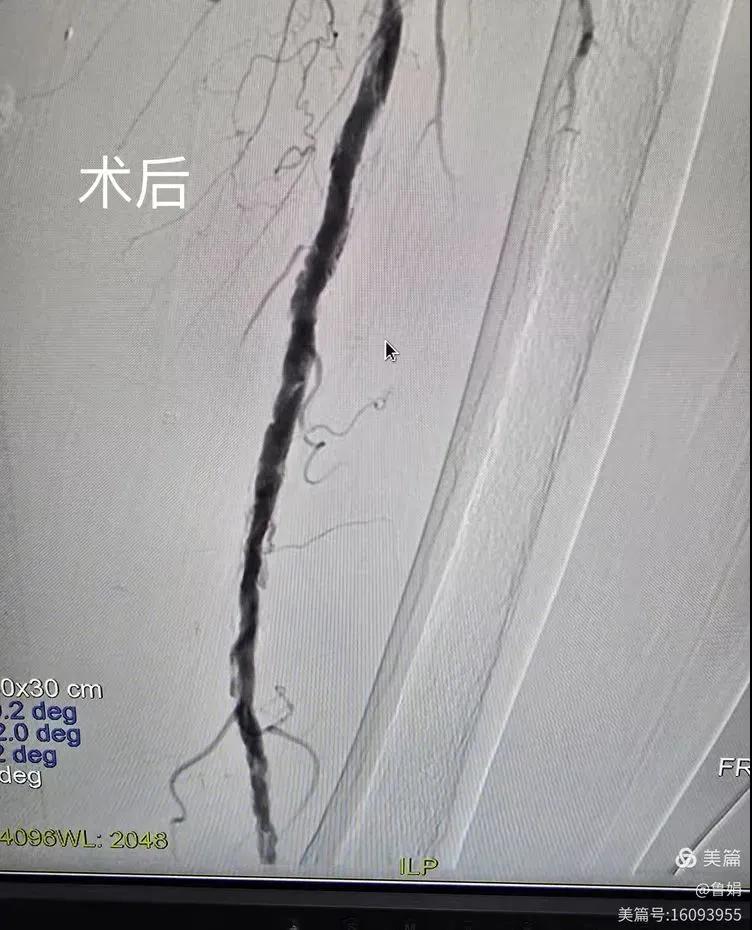

據(jù)悉,該患者,女,73歲,下肢動脈硬化閉塞癥,“以靜息痛,間歇性跛行”入院,CTA評估:股淺動脈,腘動脈間斷性多段重度狹窄,外二科血管外科團隊根據(jù)患者病情,結(jié)合檢查結(jié)果,經(jīng)過科室會診后,決定對該病人行介入治療。手術(shù)由周創(chuàng)業(yè)副主任與北大一院血管外科專家郭宏杰教授聯(lián)合開展,對股淺動脈,腘動脈重度閉塞段行血管開通+藥涂球囊擴張成形,術(shù)后狹窄明顯緩解,血流恢復(fù)!